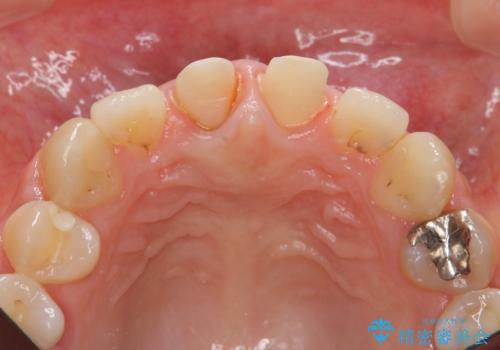

- 「 以前神経を取った歯の変色が気になる。前歯をきれいにして欲しい。」と治療を希望され来院されました。

目立つ上顎前歯に変色・大きな虫歯治療痕が見られ、審美障害を引き起こしています。